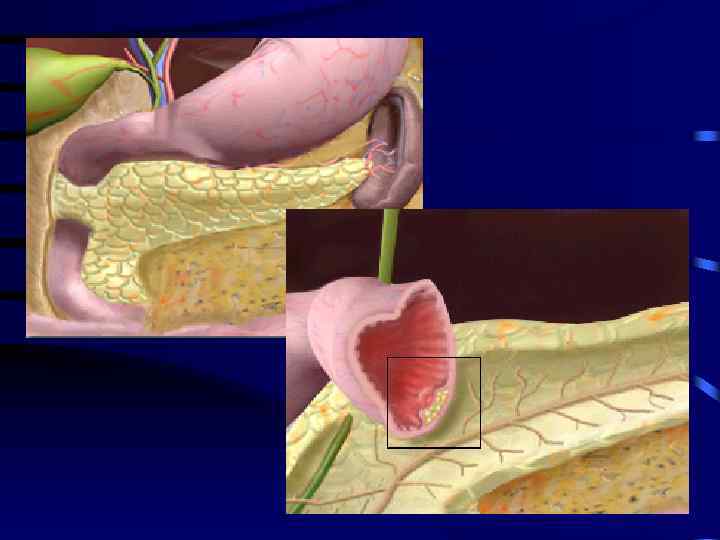

Кольцевидная поджелудочная железа • Врождённая аномалия ПЖ, при которой ткань ПЖ в виде воротника опоясывает двенадцатиперстную кишку, на разных уровнях суживая ее нисходящую часть

Методы лечения • • Дуодено дуоденоанастомоз Дуодено еюноанастомоз Гастро еюноанастомоз Пилоросохраняющее выключение ДПК из пассажа пищи по Ру • Удаление аберрантной поджелудочной железы.